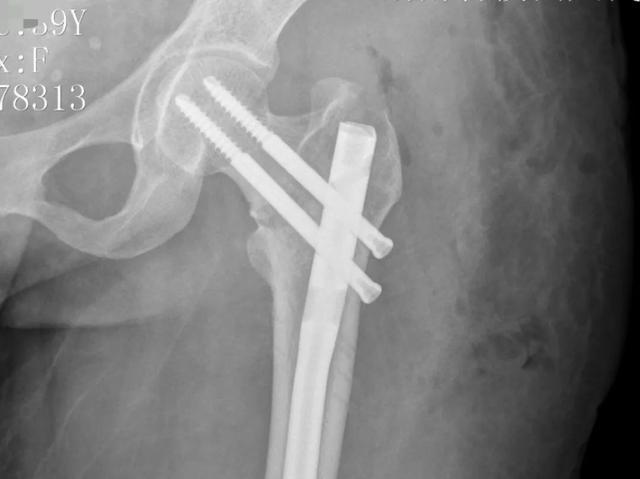

经过深思熟虑和反复推演,与王女士及其家属充分沟通后,骨二科团队决定采用微创手术方案,为王女士行闭合复位髓内钉内固定手术治疗,稳定骨折端,重塑下肢力线。

(术后)

手术室内,C型臂X光机如同医生的“第三只眼”,实时捕捉着导针在骨髓腔内的行进轨迹。主刀医生凭借着丰富的经验和精湛的技术,通过股骨近端6厘米的单一切口,利用弹性导针完成了双骨折段的“串珠式”精准复位,全程未损伤任何肌肉组织。术后王女士安返病房,目前恢复良好。